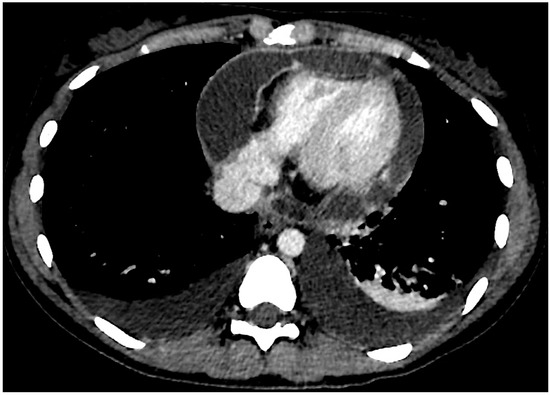

2. Case Presentation

2.1. Initial Presentation and Medical History

2.2. Current Assessment and Differential Diagnosis